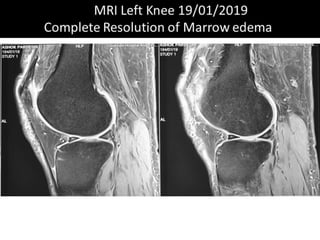

The document presents a detailed case study of a patient with transient osteoporosis of the hip (TOH) and spontaneous osteonecrosis of the knee (SONK) treated at Choithram Hospital & Research Centre in India. Over 20 years, the patient experienced multiple episodes of TOH and SONK with no history of trauma or co-morbidities, resulting in resolutions and recurrences of conditions. The information is intended for orthopedic surgery students and highlights personal experiences and case collections, with a disclaimer regarding content usage and potential controversies.